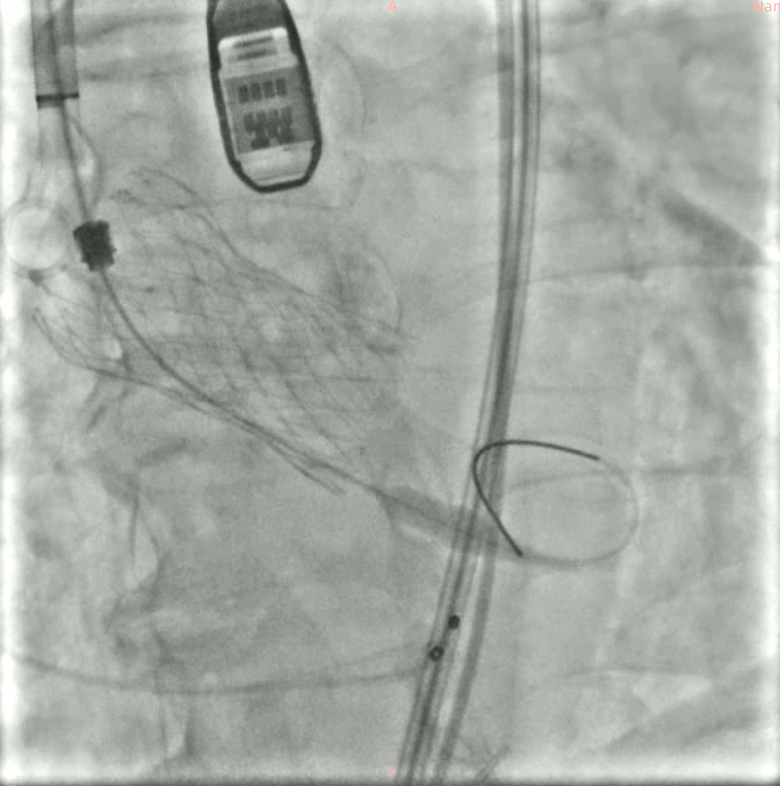

主动脉根部造影

20mm纽曼球囊预扩张

系统过弓时控制导丝避开主动脉弓部钙化。

递送系统过弓

Hat marker偏向影像左侧,符合对齐预测,C paddle位置的瓣膜对合柱将放置于左右冠开口之间,保留冠脉通路。

方向确认与预释放

瓣膜释放

瓣膜释放的前半段深度3mm,后半段受钙化挤压导致轻微下滑至5mm。

深度造影

释放前深度评估

释放后造影

导丝回退至鼻锥内释放张力避免鼻锥勾挂瓣膜。术中,Near Overlap体位下Hat marker轻微偏向右侧,确认C paddle应于左右冠脉开口中间,成功保留LCA与RCA通路。微量PVL,术后压差7mmHg;自体瓣环面瓣架呈椭圆状。环上瓣膜工作高度瓣架呈良好圆形,瓣膜开口面积良好。翻山造影确认主入路无严重血管并发症,手术结束。